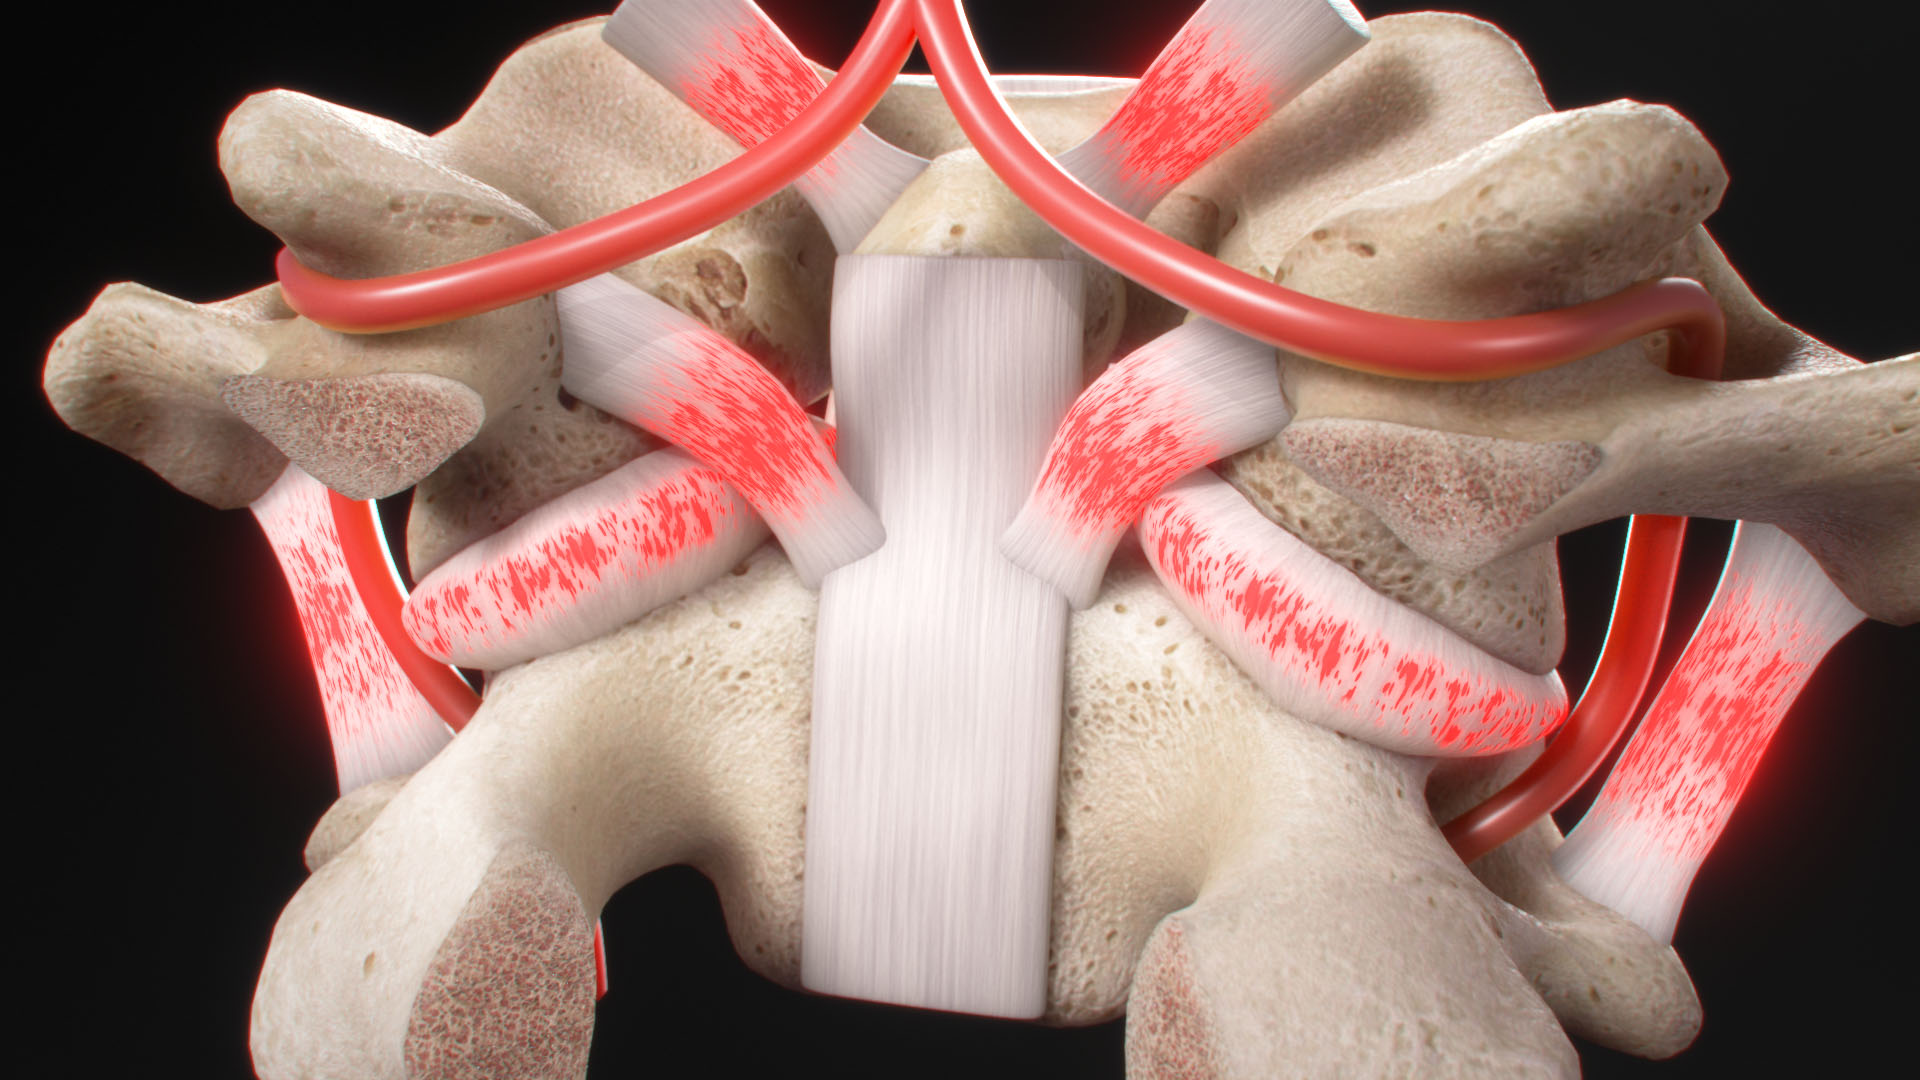

The world of medicine and healthcare is filled with complex concepts, intricate procedures, and marvels of human anatomy. Translating these intricate details into accessible and engaging visuals is no easy task. Ghost Medical Animation's team of animators and medical artists excel at merging the worlds of art and science, distilling complex medical information into eye-catching and informative illustrations.

With their keen eye for detail, the artists transform medical data, research findings, and clinical knowledge into visually appealing content. Each image and frame in their gallery serves as a bridge between the scientific realm and the general public, helping people comprehend medical concepts with ease while leaving them awe-inspired by the beauty of the human body's inner workings.

One of the most striking aspects of Ghost Medical Animation's Image Gallery is the diversity of subjects and medical fields covered. Whether it's depicting the intricacies of cellular biology, illustrating the intricacies of surgical techniques, or presenting the mechanism of action of pharmaceuticals, their artists are adept at handling a wide range of medical topics.

The team's expertise isn't limited to still medical illustrations; they are also masters of animation. They bring medical concepts to life through fluid and captivating animations, making it easier for both professionals and laypeople to understand complex medical processes. Through their skillful use of motion, the animations breathe life into scientific ideas, helping viewers envision dynamic physiological processes and medical advancements.